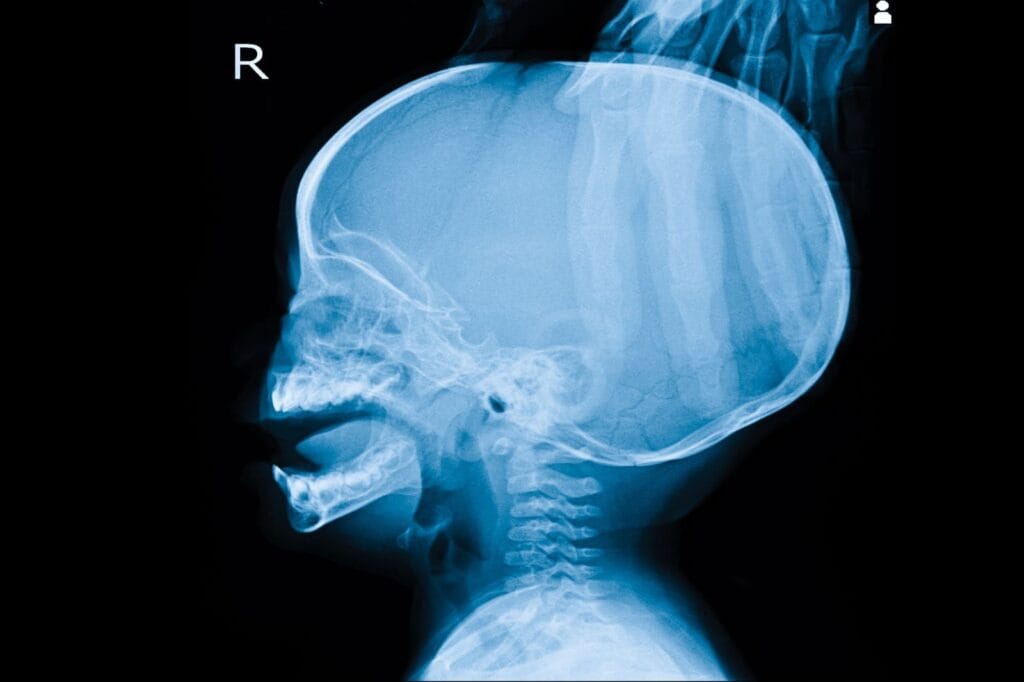

Diagnosis Hidrosefalus

Pemeriksaan rutin yang dikerjakan untuk mengetahui penyakit hidrosefalus dan sekaligus mencari penyebab yang mendasari adalah menggunakan CT scan atau MRI kepala. Dapat tim medis kerjakan dengan dan tanpa kontras sesuai dengan kebutuhan.

Selain itu, tes pencitraan seperti ultrasonografi (USG) dapat menjadi pemeriksaan pertama bagi bayi karena prosedurnya sederhana dan minim efek samping. Pada pemeriksaan ini, dokter akan meletakkan alat USG di atas bagian lunak kepala bayi.